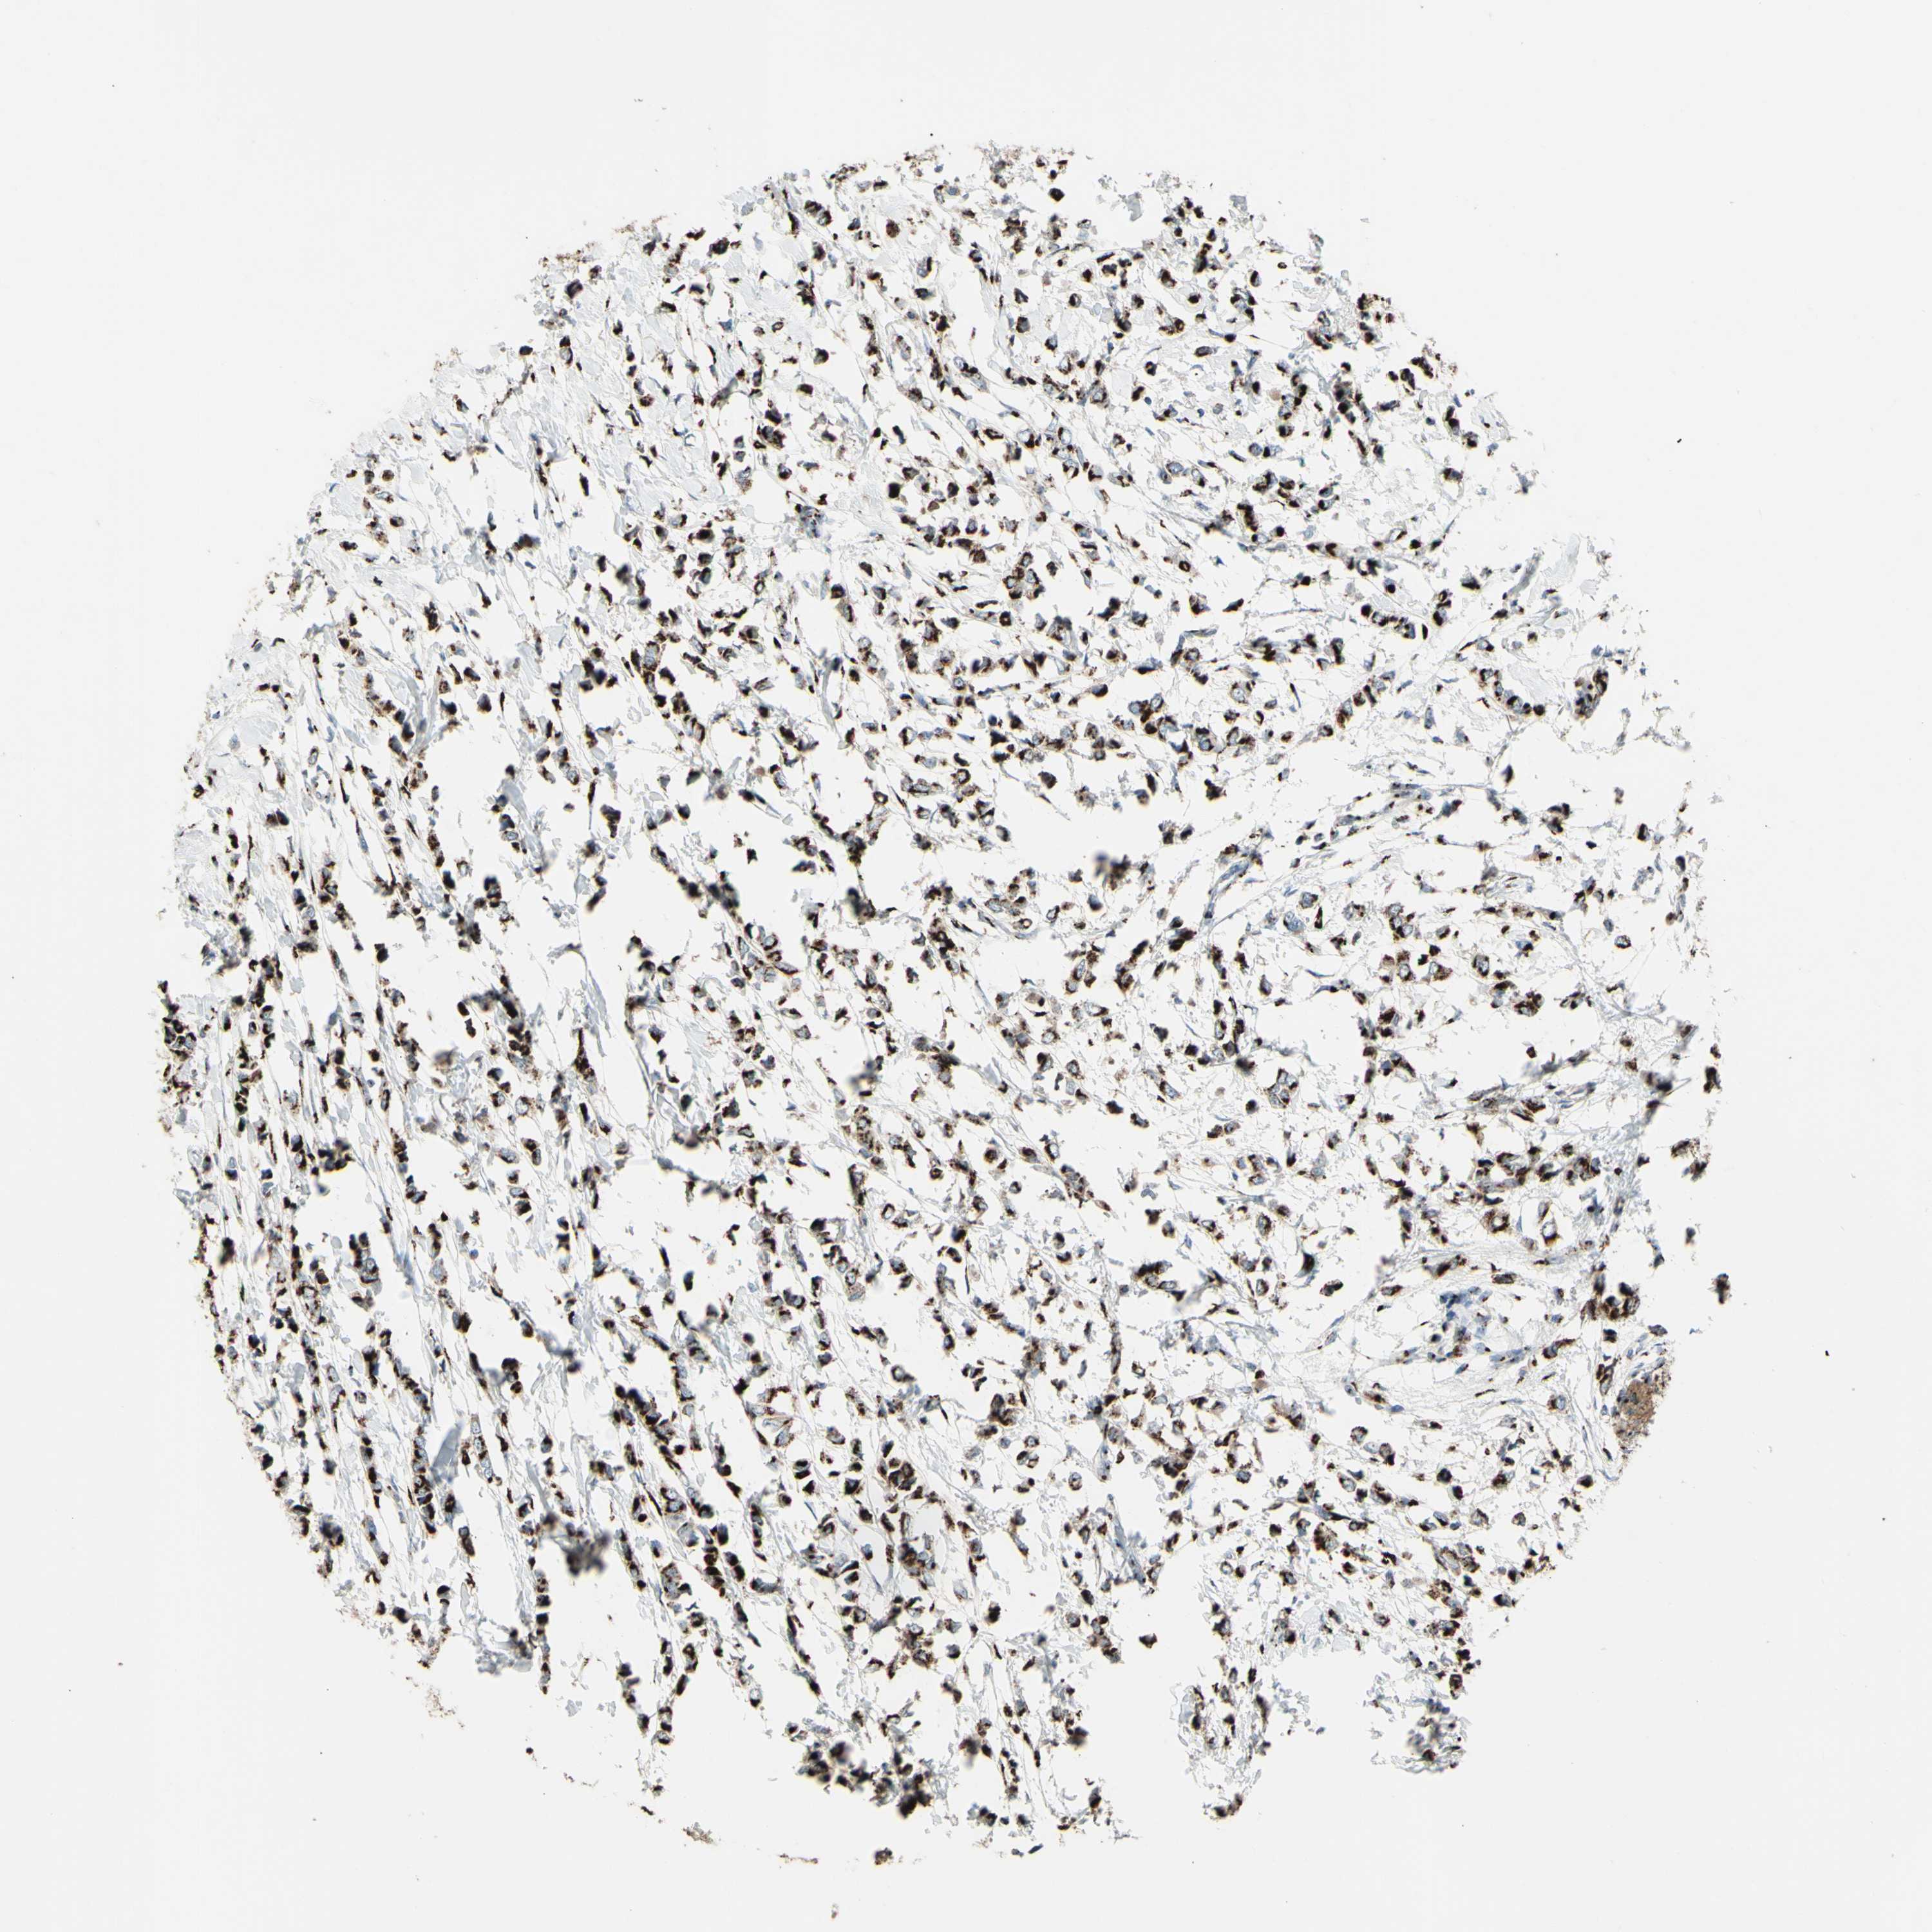

BRCA TCGA BRCA VALIDATION PROTEIN EXPRESSION

ANTIBODIES

AND

VALIDATION